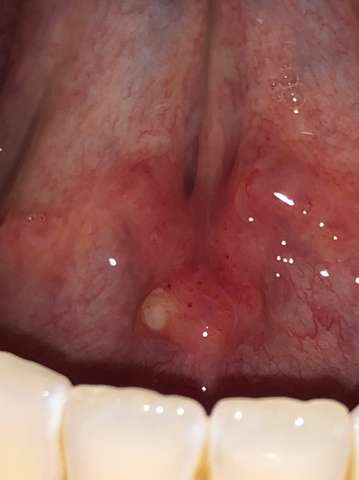

Roter Pickel Unter Zunge Bei Vierjahriger Mit Foto Gesundheit Erziehung Online Forum